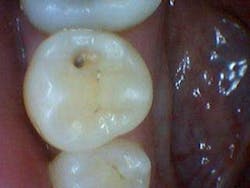

In the aforementioned case, the reading on the occlusal surface was a 46 (see Figs. 3 through 8 below). Look at what was underneath. Surprised? I often wonder how many times per day lesions like this are going undiagnosed.

After the final smear layer was removed, the tooth was filled with Grandio resin. Afterwards, I showed the photographs to my patient. Any doubt that he had was immediately erased. Most importantly, he was grateful and his trust in me was solidified.